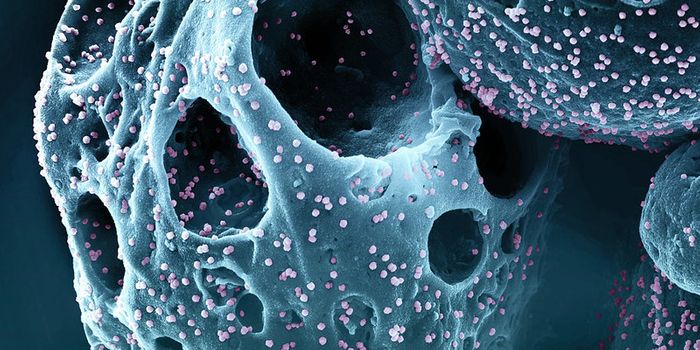

SEP 05, 2024Cell & Molecular BiologyCorynebacterium matruchotii ia a common bacterium that lives in human dental plaque; a colony is seen in this image by S ...